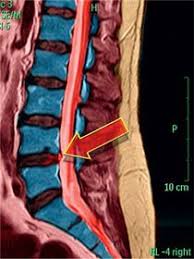

Im Vordergrund steht die schmerzlindernde Behandlung der Beschwerden damit man so aktiv wie möglich bleiben kann. Ein Bandscheibenvorfall kann unbemerkt bleiben aber auch zu. Die Genesung lässt sich durch die Schmerztherapie zwar nicht beschleunigen. Erstes Mittel der Wahl ist die konservative Therapie. Bis dahin können verschiedene schmerzlindernde Behandlungen helfen mit den Beschwerden zurechtzukommen. Andernfalls erfolgt eine direkte Überweisung an einen Orthopäden. Wie ein Bandscheibenvorfall behandelt. Durch Druck- und Fehlbelastungen des vorderen Bandscheibenanteils tritt Bandscheibenmaterial in der LWS normalerweise nach hinten oder hinten seitlich aus. Wie wird ein Bandscheibenvorfall behandelt.

Bandscheibenvorfälle werden nicht immer operiert. Was ist ein Bandscheibenvorfall. Andernfalls erfolgt eine direkte Überweisung an einen Orthopäden. Durch Druck- und Fehlbelastungen des vorderen Bandscheibenanteils tritt Bandscheibenmaterial in der LWS normalerweise nach hinten oder hinten seitlich aus. Dabei wird die Bandscheibe entfernt und ein Platzhalter entweder eine Bandscheibenprothese oder ein Cage Titan- oder Kunststoffring eingesetzt. Wie wird ein Bandscheibenvorfall behandelt. Bandscheibenvorfälle werden nicht immer operiert.